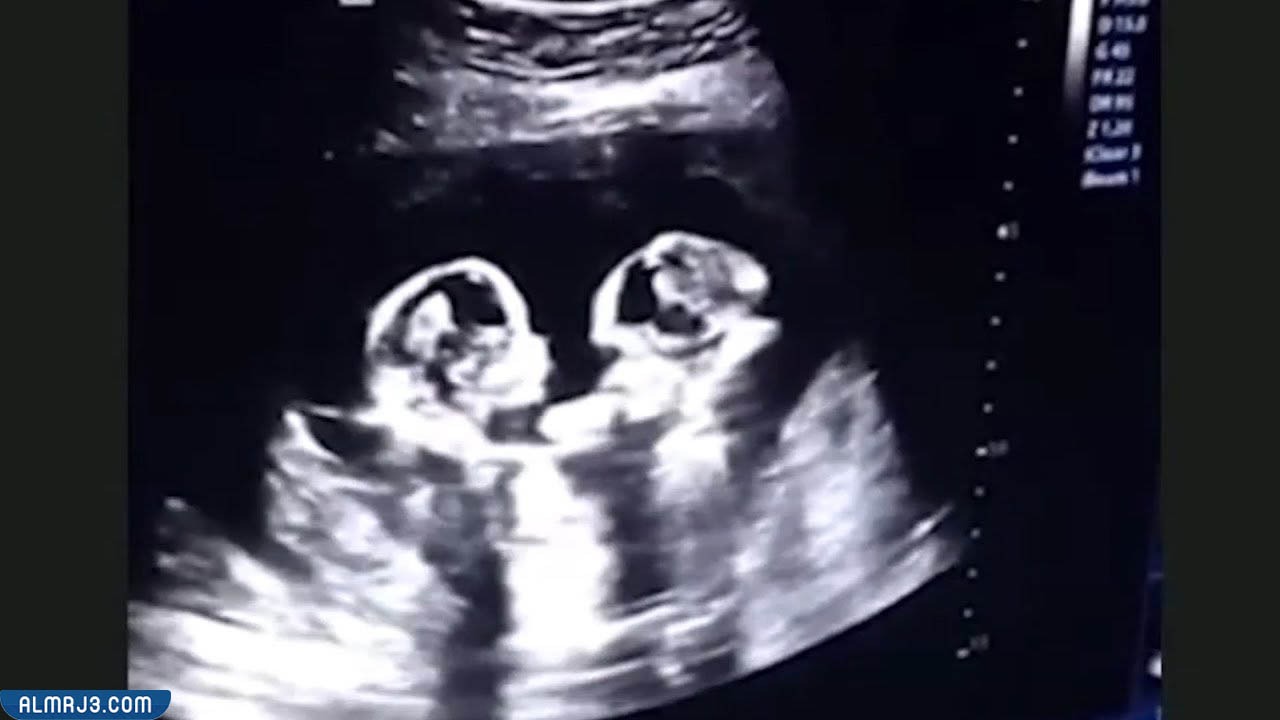

خطورة ولادة التوأم في الشهر الثامن تعتبر أحد أهم الأمور التي ترغب الأمهات الحوامل بأكثر من طفل واحد الإلمام بها، نظرًا لأنه في الكثير من الحالات يصاحب ميلاد التوأم مشاكل صحية تتعلق بموت أو مرض أحد الجنينين أو حتى بحدوث مشاكل صحية للأم، لذلك سيقوم موقع المرجع في هذا المقال بتوضيح المشاكل التي تتعلق بولادة التوأم قبل موعدهم الطبيعي، خاصة الولادة في الشهر الثامن.

تطورات الأجنة التوأم في الشهر الثامن

عادة ما يتطور الأجنة التوائم في الشهر الثامن التطورات الآتية:

- يزداد وزن الأجنة في الشهر الثامن من الحمل.

- في الشهر الثامن يخرج الشعر من فروة الرأس.

- يبدأ مخ الجنين في الانتهاء من التكوين الذي يكون داخل الرحم.

- يبدأ الجنين في استيعاب الأشياء من حوله بصورة بسيطة، كتفهم معنى الصوت ورؤيته للضوء وتمييز الروائح وغيرها.

- تصبح عظام الجنين أكثر صلابة باستثناء منطقة الرأس، إذا تظل لينة لتسهيل عملية الولادة.

- تصبح الرئة قادرة على القيام بعملية التنفس بصورة طبيعية بعد إتمام الولادة.

- تنخفض رأس الجنينين إلى الأسفل تمهيدًا لحدوث عملية الولادة.